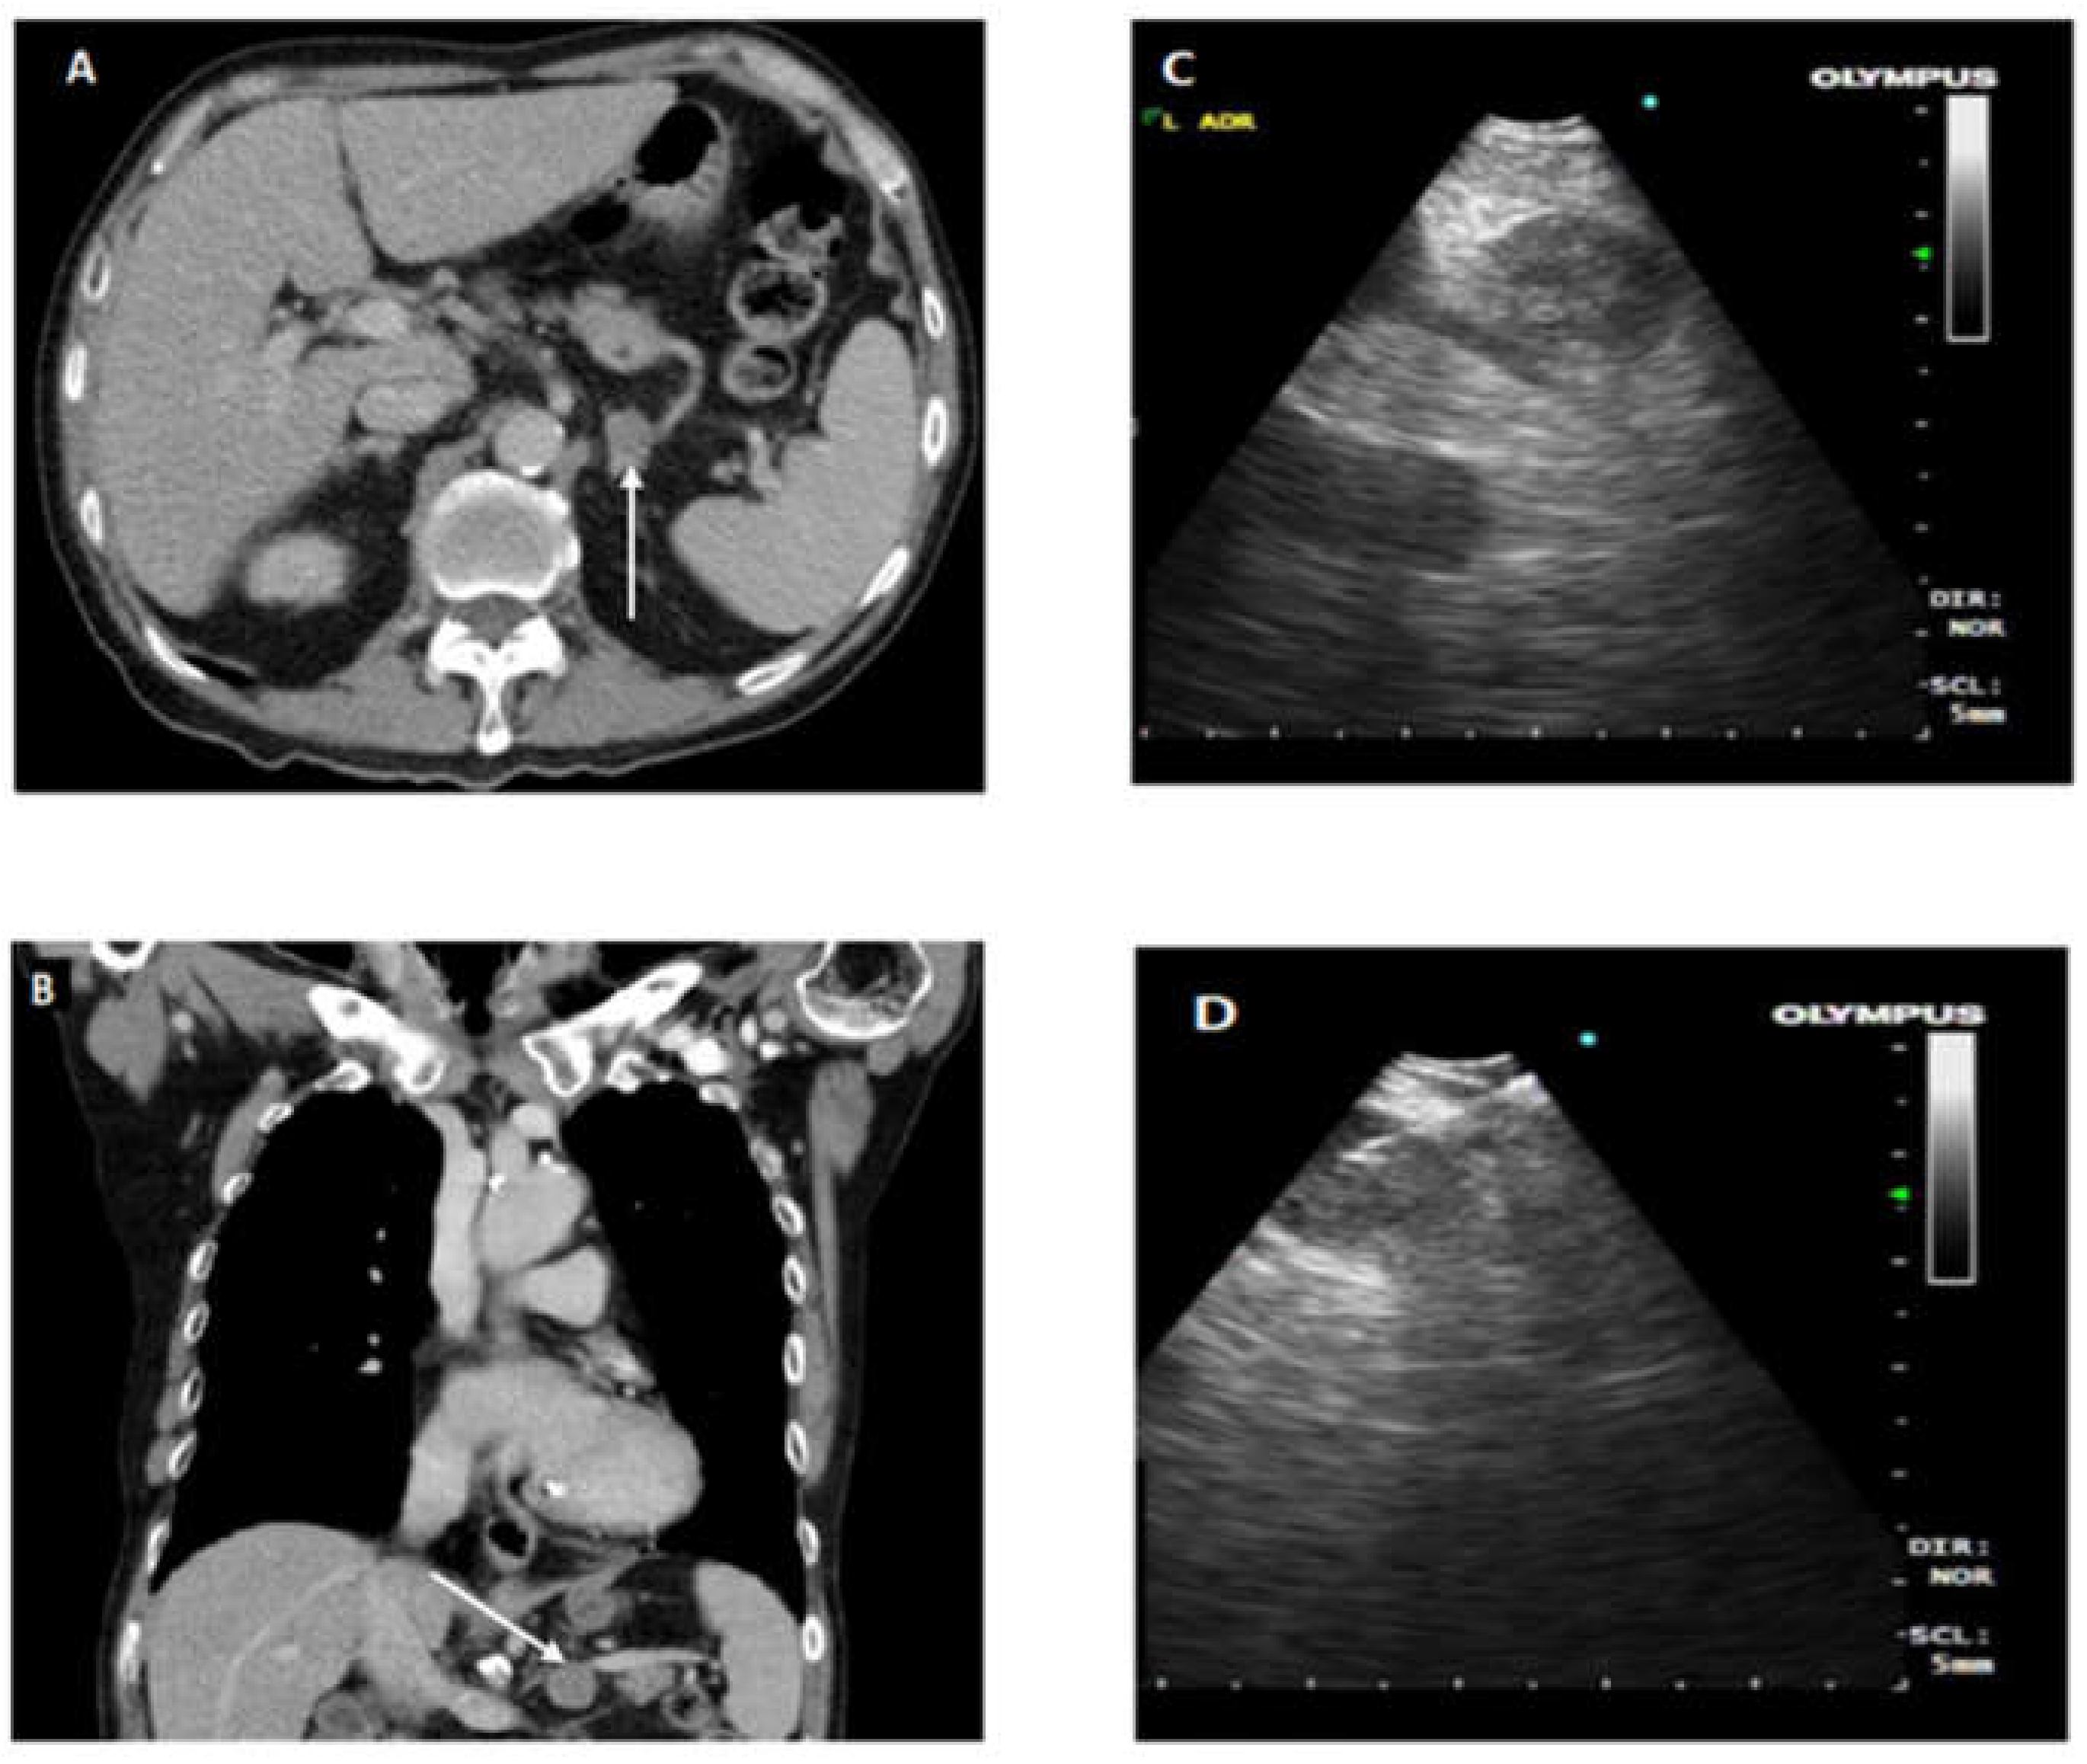

Cases that required EUS-B FNA after EBUS assessment or were assessed to require only EUS-B FNA had standardized EUS-B procedure as described previously [3,4]. EUS-B was introduced into esophagus by mouth and oropharynx. In accordance with EUSAT assessment method described by Konge et al. [10], the order of identification of landmark is as follows: liver, adrenals, coeliac axis, station 7, and then station 4 left. Needle sheath is pushed out and visualized before puncturing the lymph node under ultrasonic visualization. After removal of stylet, multiple needle aspirations are made. Needle is fully retracted before removal from EBUS scope for specimen collection. To prevent upstaging of lung cancer, all FNA biopsies were done in following order of M1 distant metastases followed by N3, N2, and N1. Ultrasound images of lymph node stations and fine needle aspirate of lymph nodes are recorded and kept in patient electronic records. Close attention and supervision are given to needle handling for assurance of patient and equipment safety. Figure 1. provides CT and endoscopic ultrasound images for illustration of EUS-B FNA.

Figure 1. (A,B) CT axial and coronal sections, respectively. Arrowhead indicates enlarged left adrenal gland (LAG); (C) demonstrates EUS-B image of LAG; (D) illustrates EUS-B FNA of enlarged LAG with needle in target lesion.